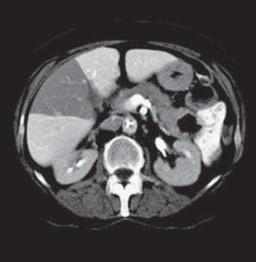

Kazuistika I (segmenty jaterní tkáně)